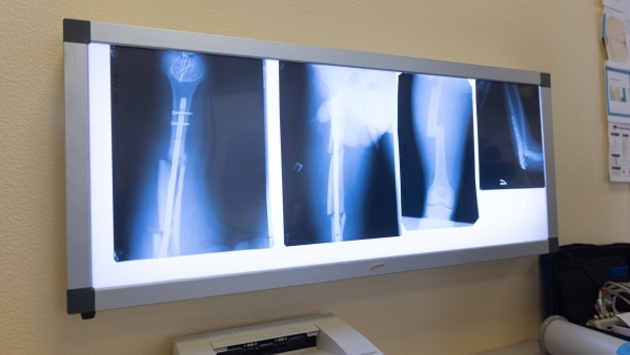

«Мы впервые реализовали в регионе большой проект цифровизации рентгеновского оборудования: приобрели как новую технику – в том числе маммограф, рентгеновские установки, – так и аппараты для оцифровки уже имеющегося оборудования. Работа масштабная, важная. Все понимают, насколько современные цифровые технологии повышают качество и скорость диагностики», – сказал Текслер. По данным аудита, если на начало 2025 года лишь 38% аппаратов были цифровыми, то к 1 января 2026 года этот показатель достиг 56%. На эти цели из областного бюджета было направлено более 230 миллионов рублей. Ключевой целью проекта является формирование единой цифровой базы исследований. Все рентгеновские снимки и заключения хранятся в электронном виде, что обеспечивает защищенный доступ для врачей из любого медицинского учреждения области и позволяет удаленно подключать ведущих экспертов к консультациям по сложным случаям. По словам министра здравоохранения региона Татьяны Колчинской, новые установки не только улучшают качество изображения для точной диагностики, но и значительно сокращают время обследования. Ранее «ФедералПресс» о том, что губернатор Текслер провел первое заседание совета главврачей в Копейске. Фото: ФедералПресс / Иван Кабанов